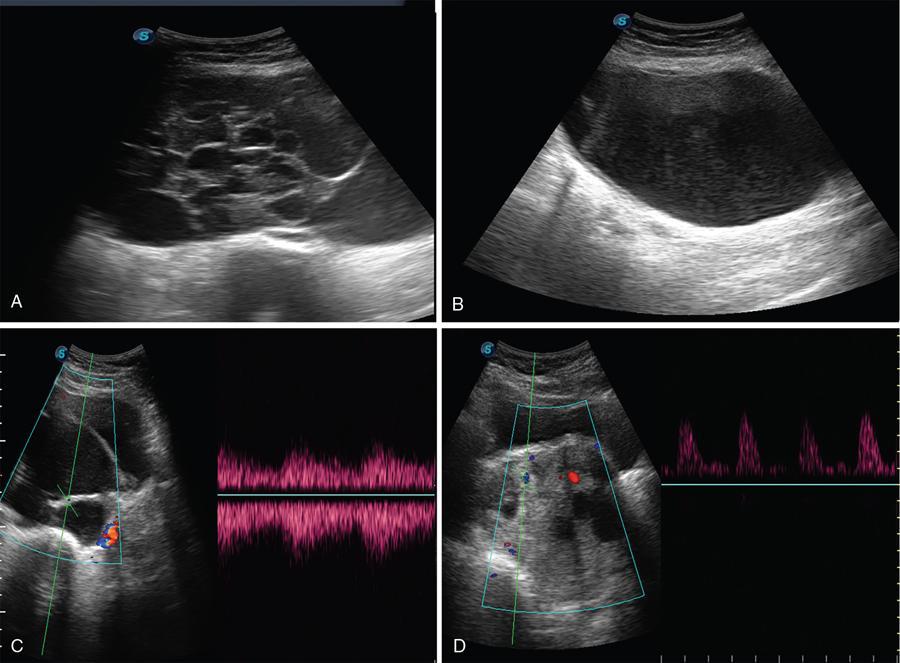

Bladder is visualized as a round or oval shaped anechoic fluid filled structure in the midline of pelvis (Fig. 11.4.1.3A).

Ultrasonography shows distal ureteral jet. Doppler imaging shows the stream of urine entering the bladder through the ureteral orifice (Fig. 11.4.1.3B).